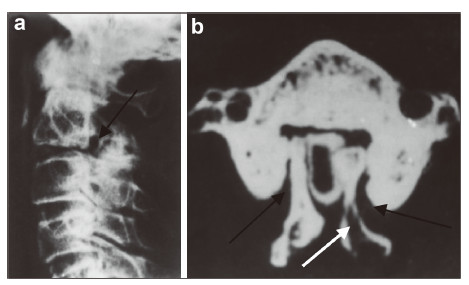

| Figure 2 A 26‐year‐old man presented with bilateral C3 spondylolysis. (a) Lateral view plain radiography showing a hypoplastic articular mass and spinal process at C2(black arrow).(b) Iodine contrast CT showing bilateral clefts between the articular pillar and the facets of C3 as well as spina bifida (white arrow). |